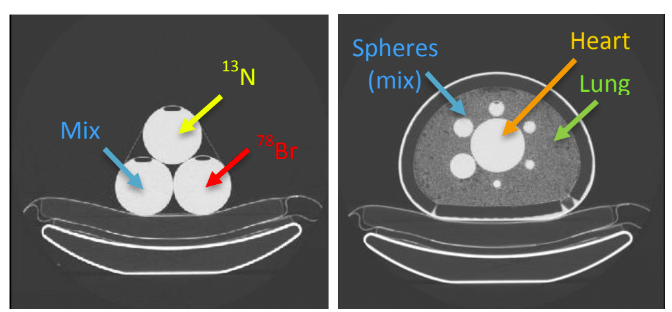

| ABSTRACT | Introduction: Simultaneous in-vivo imaging of several biological processes may improve oncological, neurological and cardiovascular studies by providing complementary information obtained under the same exact conditions and coregistered in space and time. Standard PET imaging does not allow multiplexed acquisitions, as all annihilation photons have the same energy. We developed a technique called multiplexed PET (mPET), which uses a tracer labelled with a pure positron emitter (such as 18 F, 13 N, 11 C), and a tracer labeled with a positrongamma emitter (such as 124 I, 76 Br, 82 Rb, 86 Y). Positrongamma emitters generate a significant number of triplecoincidences , which allows them to be differentiated from the standard PET radionuclides . In this work, we evaluated the performance of mPET using phantom and animal experiments. |

| ABSTRACT | Multiplexed PET (mPET) is a new imaging technique compatible with any existing PET scanner which allows simultaneous imaging of two PET tracers in vivo. In this work we present initial results of a new procedure to measure liquid absorption (LA) in the airways, a promising biomarker for evaluating treatment response in lung diseases. We performed dynamic PET imaging in the lungs of 10 pigs in a clinical PET scanner using inhaled 13N-NH3 and 76Br-Albumin as tracers.

Triple coincidences in PET can be used to enable the simultaneous imaging and separation of radiotracers labeled with standard positron emitters (such as 13N) and positron-gamma emitters (such as 76 Br). We have previously shown that multiplexed PET can be achieved without any kinetic modelling or hardware modification, and therefore it can be used in most current PET scanners. The goal of this study was to demonstrate that this methodology can be applied to solve important clinical needs, such as the quantitative measurement of the liquid absorption in the airways, a new biomarker for the treatment response of Cystic Fibrosis (CF) patients. |